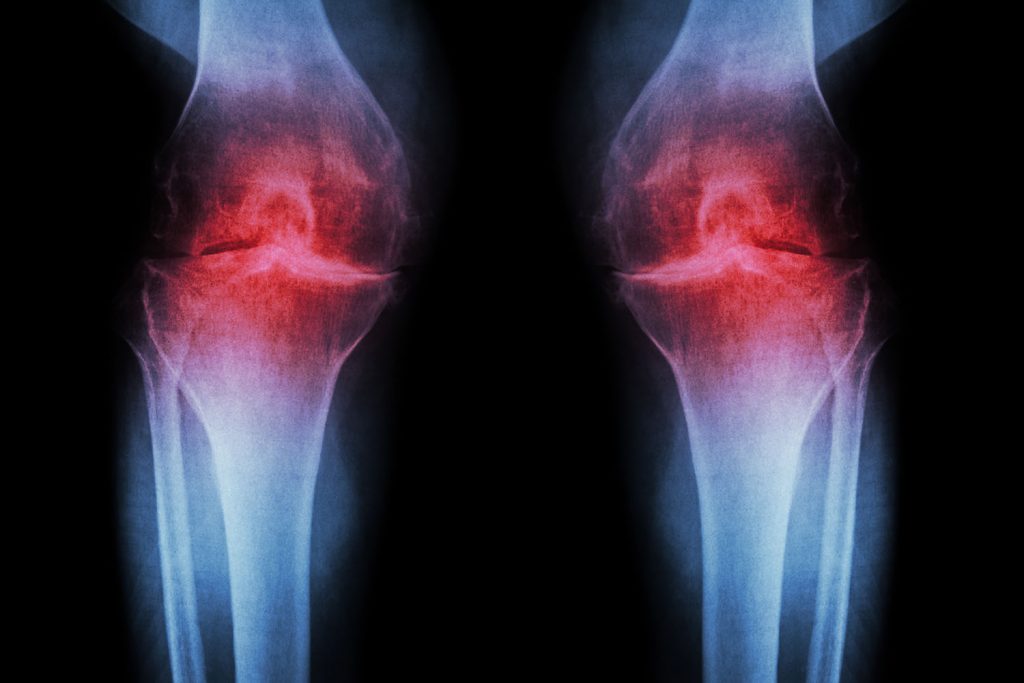

Osteoartrita este o afectiune degenerativa caracterizata prin distrugerea in timp a cartilajului care protejeaza suprafata articulara. Odata ce cartilajul se subtiaza, oasele se ating si la fiecare miscare apare fenomenul de frecare intre acestea, lucru care provoaca durere. Aceasta afectiune este cea mai comuna cauza a durerilor articulare la varstnici, putand afecta atat articulatiile mari, cat si pe cele mici. Din pacate, osteoartrita in stadiile avansate este extrem de invalidanta, astfel incat calitatea vietii acestor pacienti este afectata.

Poliartrita reumatoida este o afectiune inflamatoare autoimuna, ce afecteaza articulatiile mainilor si picioarelor si apare frecvent la populatia cu varsta cuprinsa intre 25 si 50 de ani. Cauza acestei boli este o alterare in sistemul imunitar care ataca articulatiile, cu timpul aparand eroziuni ale cartilajului si oaselor. Odata ce boala avanseaza, au loc tumefactii si deformari articulare extrem de dureroase si invalidante. Aproximativ 30% dintre cei afectati prezinta si noduli reumatoizi specifici. Desi tabloul clinic al acestei boli este destul de usor de recunoscut pentru diagnosticul de certitudine, este nevoie de analize de laborator (markeri specifici).